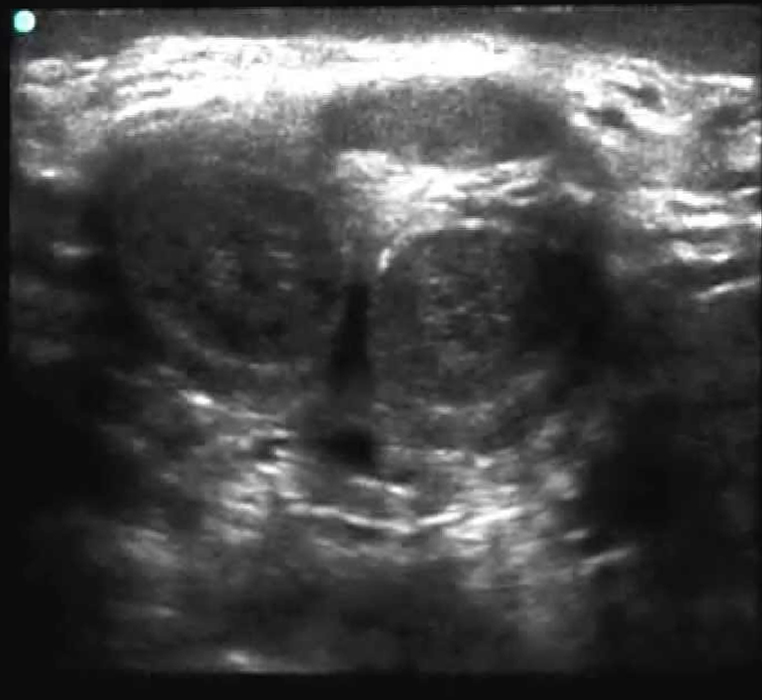

Biopsia Prostática Transrectal Ecodirigida